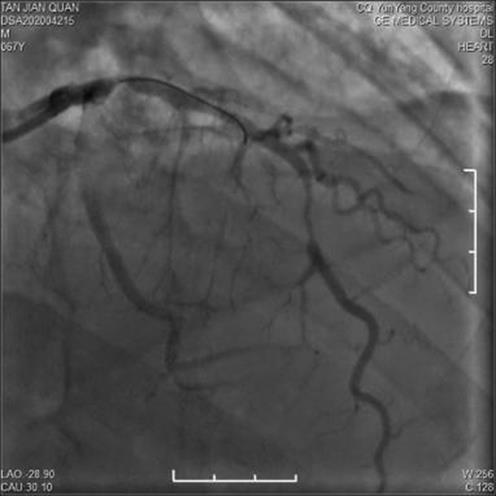

• 疑似雷帕霉素药物洗脱支架术后Kounis综合征1例

2024, 49(1):97-100. DOI: 10.13406/j.cnki.cyxb.003409

摘要 (42) HTML (15) PDF 1.14 M (104) 评论 (0) 收藏

摘要: